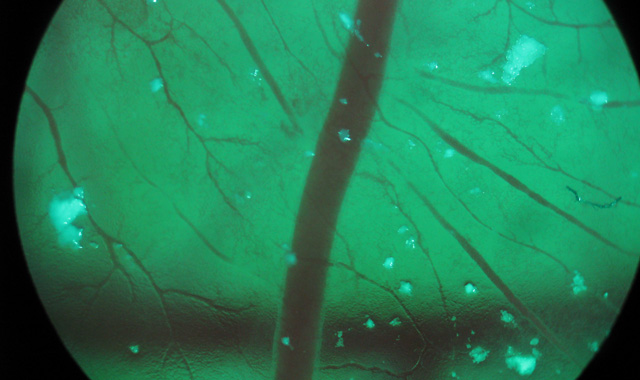

Nanoparticles in Embryonic Models

Nanoparticle toxicology is an increasingly popular and important area of study in adult organisms.  However, the effects of nanoparticles on embryos have not been fully studied. Our group works on injecting fluorescent nanoparticles, such as quantum dots, polystyrene fluospheres and lipid nanoparticles, into chicken embryo models. Our goal is to study potential toxicological effects, such as aggregation and uptake into embryonic blood vessel walls and organs.